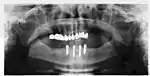

Panorex radiograph showing implants

Xray of four Straumann implants and abutments